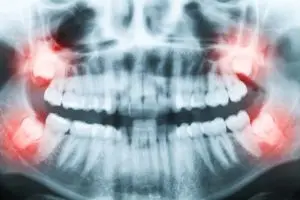

What Are Wisdom Teeth?Wisdom teeth are a third set of molars. Most people know by their 20s whether they have wisdom teeth or not. Some people may not have a full set of four and some people don’t have any wisdom teeth at all. Scientists understand that the need for the last set of molars has diminished over time due to softer foods and different culinary habits. This makes the size of our jaws smaller and the need for the molars decrease. For this reason, impacted wisdom teeth can be a real pain.

There are different levels of critical care with wisdom tooth emergencies. Sometimes the tooth partially erupts above the gum line and causes an infection known as pericoronitis. In some cases, the tooth will partially erupt to the surface or stay beneath a soft layer of tissue where food may become lodged in it and cause an infection called operculum; this is also pericoronitis.

Complications of Wisdom Tooth Infection When Not Handled ImmediatelySometimes the infected wisdom tooth causes other dental problems and the need to handle the infection becomes urgent. If the wisdom tooth erupts at an adjacent angle to another molar, it could cause deep periodontal pockets, receding gums, and gum disease. The tooth will need to be removed so that you don’t lose teeth that are essential to your dental hygiene.

If your wisdom tooth erupts and crowds other teeth, it will need to be removed before too much damage or decay is caused.